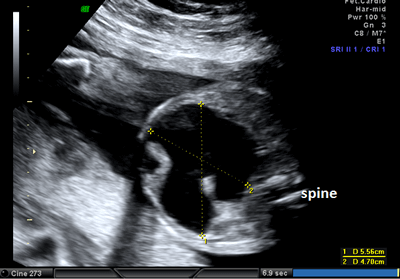

A 26-year-old pregnant women, gravida 1, para 0, was admitted to our prenatal diagnosis centre for detailed ultrasonography examination. Obstetric history was unremarkable. A single fetus was detected at 26 gestational weeks. A presacral located cystic mass measuring 45 × 55 × 40 mm was seen on ultrasound examination (Fig. 1). On doppler ultrasound, the cystic structure with both umbilical arteries around was considered an enlarged distally obstructed fetal bladder initially (Fig. 2). However, the bladder was later identified more superiorly. The amniotic fluid index was 129mm. Diagnosis of the cystic mass was unclear and a fetal MRI was performed, which delineated a large cystic mass with minimal internal echogenicity area, the type IV teratoma (big arrow head). The white arrow demonstrates a cystic mass considered as a hydrometrocolposis (Fig. 3).

Figure 1: The pelvic cystic structure (55 x 47 mm) with irregular borders. |